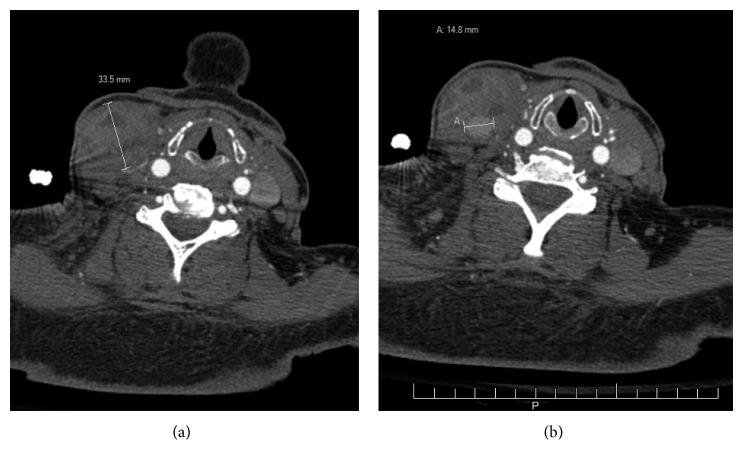

A 63-year-old female with multiple comorbidities presented with a firm 7 cm tender mass located in the right neck. Ultrasound showed pseudoaneurysm and a 7 × 3.3 × 4 cm multilobular hematoma in the location of the previous central line. CTA showed a corresponding heterogeneous mass. Serial imaging demonstrated enlargement over 2 weeks. Angiogram showed contrast blush off of the SBSTA.

SBSTA was embolized using glue. Repeat angiogram showed embolization and no contrast blush. One month later, the mass was no longer pulsatile but present on physical exam. CTA showed decreased size. 8 months later, her neck was soft without mass.

一名患有多种合并症的63岁女性,右颈部出现一个质地坚硬、压痛的7厘米肿块。超声显示假性动脉瘤以及位于先前中线位置的一个7×3.3×4厘米的多叶血肿。CT血管造影(CTA)显示有一个相应的不均匀肿块。连续成像显示该肿块在2周内增大。血管造影显示SBSTA有造影剂外溢。

使用胶水对SBSTA进行栓塞。重复血管造影显示栓塞成功且无造影剂外溢。1个月后,肿块不再有搏动,但体格检查时仍存在。CTA显示肿块尺寸减小。8个月后,她的颈部变软,无肿块。